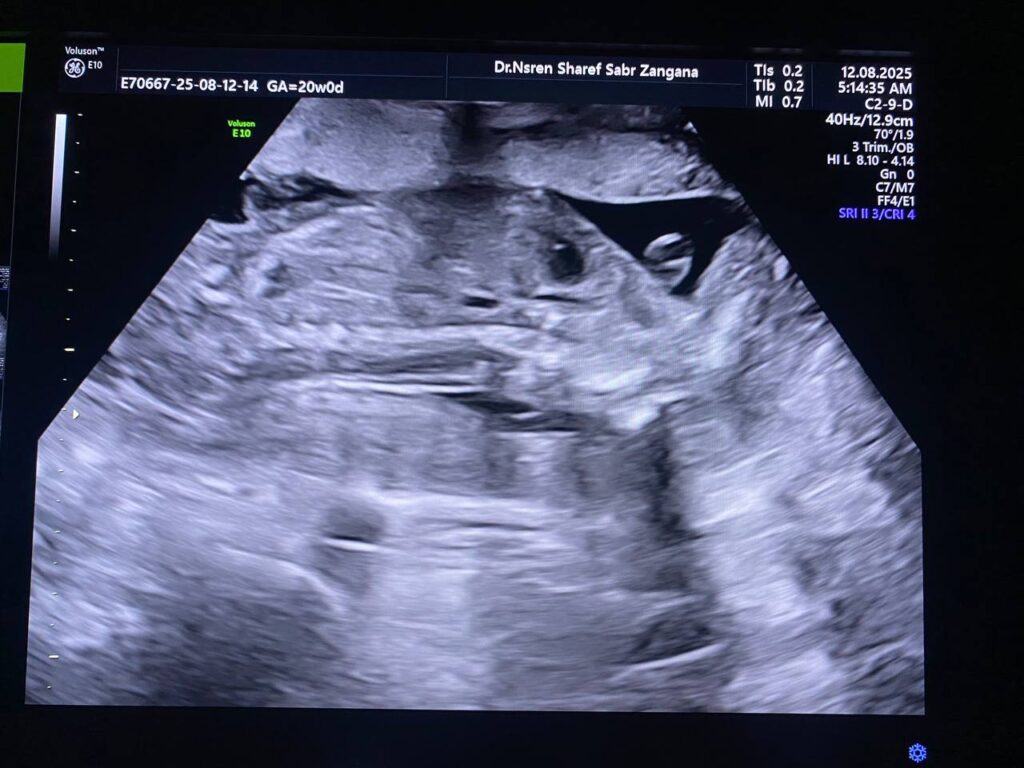

Multiple congenital anomaly seen , small chest , curve long bones , short limbs , kyphoscoliosis, congenital heart disease , edematous skin, picture mostly of thanatophoric dysplasia

F.L. = 16w+2d